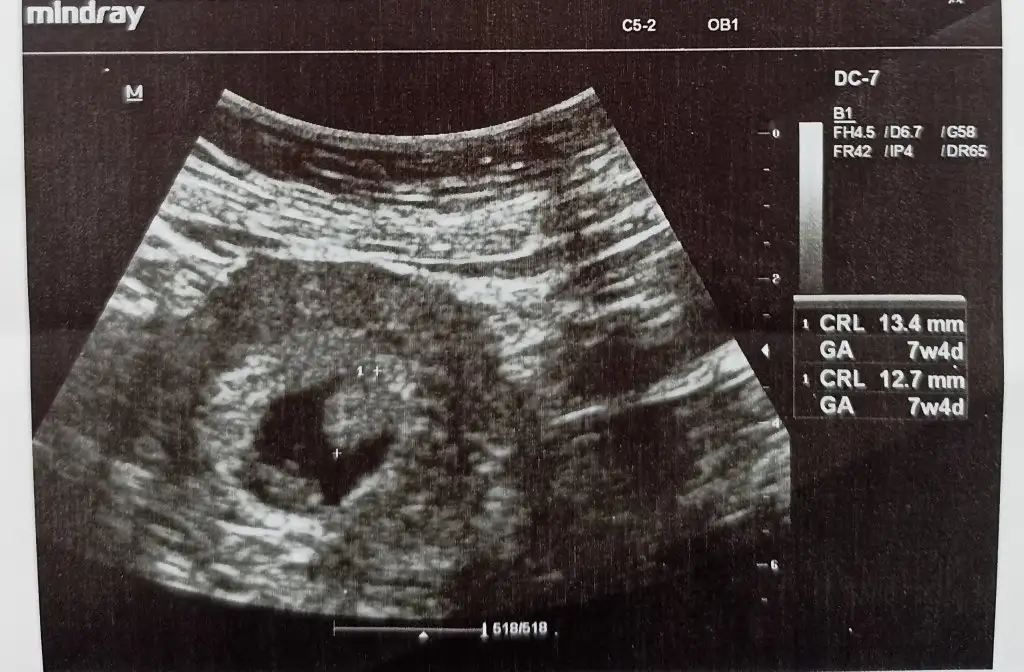

Merhaba arkadaşlar. Yeni üyeyim ilk defa buraya yazıyorum yardımcı olursanız sevinirim. 7+4 haftalık hamileyken doktora gittim ve eklediğim ultrason görüntüsünü verdi doktorum. Tek kalp atışı duyduk ama kese içinde bir şey daha vardı. Devlete gittiğim için doktorum ultrason cihazının eski olduğunu, eğitim araştırmaya gitmem gerektiğini söyledi. 3 gün sonra oraya gittim oradakiler de beklemem gerektiğini söylediler. İlk hamileliğim düşük olduğu için biraz tedirgin oldum. 4 gün sonra kontrolüm var ama merak etmeden de duramıyorum, böyle bir durum yaşayan var mı?

yolk sac değil mi o? 12. Haftaya kadar kaybolacak.